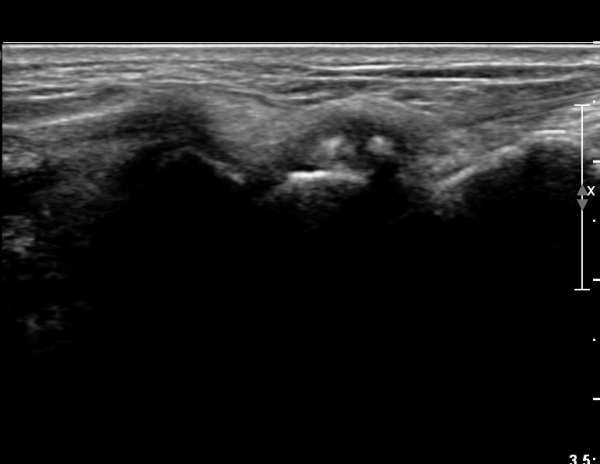

¼Õ¸ñ ¹èÃà, ̫̿ Á¾´Ü¸é°Ë»ç¿¡¼ ô°ñ¼ö±Ù°ñ °üÀý³» ¼ö¾×Àú·ù¿Í »ï°¢°ñ Ç¥Ãþ¿¡ °ñ±ØÀÌ °üÂûµÈ´Ù(»çÁø 1),